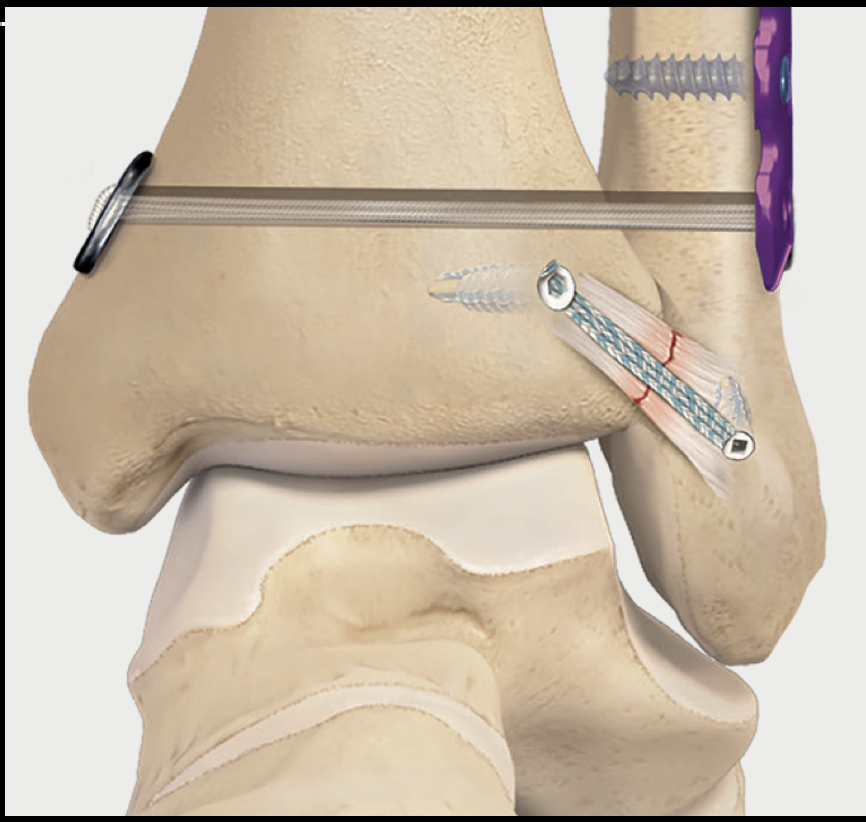

Fig 2. Diagram of AITFL internal brace and tightrope construct.

AITFL Internal Brace Reconstruction

The internal brace is a strong synthetic tape — roughly the thickness of a shoelace — anchored into the fibula and tibia at the exact position of the torn AITFL. It acts as an internal scaffold while the ligament heals, taking the load off the repair during early rehabilitation.

Where possible I also directly repair the torn AITFL underneath the tape — a repair-and-augment approach that gives the best healing result. The tape remains in place permanently and does not need to be removed routinely. This technique is well-suited to Grade I–II injuries and isolated AITFL tears (5,6).

Syndesmotic Tightrope Stabilisation

For moderate to severe injuries, a tightrope device provides more robust stabilisation across the full width of the joint. A small tunnel is drilled through both the fibula and tibia, and a strong suture tape is threaded through with small metal buttons on either side. When tensioned, it compresses the two bones back together, restoring normal joint width — like a zip tie pulling the bones into alignment.

Unlike metal screws that were used in the past, suture tape tightropes do not routinely need to be removed — they are flexible enough to allow the small natural movement at the syndesmosis without breaking (7).

In many patients with Grade II–III injuries I use both techniques together (8): an internal brace for the anterior ligament reconstruction and a tightrope for compression and rotational control. This combined approach provides robust early stability and supports a faster return to sport.